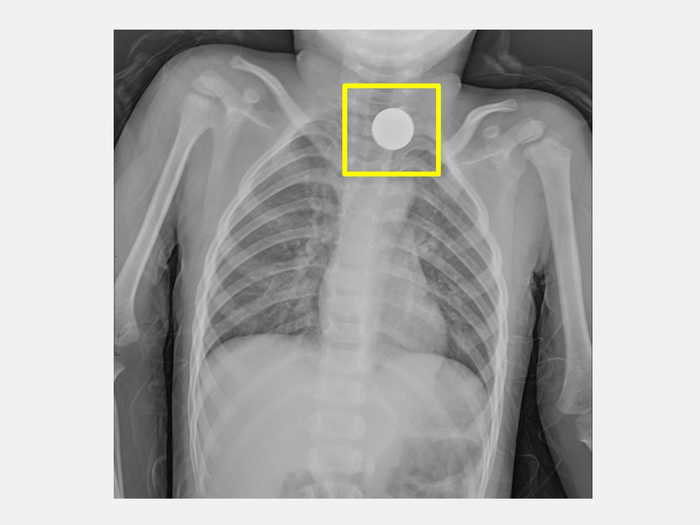

圖一:胸部X光顯示在食道處有一個環狀扁平異物(方框處),診斷為小兒食道異物。